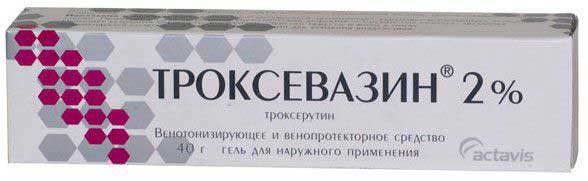

- Венотонизирующие средства (например, Троксевазин).

Троксевазин

Препарат создан на основе натуральных растительных ингредиентов, эффективно борется с воспалительными процессами, снижает отечность и восстанавливает проницаемость сосудов.